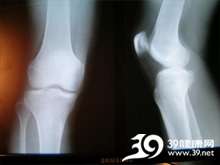

膝盖扭伤

膝盖扭伤(sprain)是指四肢关节或躯体部的软组织(如肌肉、肌腱、韧带、血管等)损伤,而无骨折、脱臼、皮肉破损等情况。临床主要表现为损伤部位疼痛肿胀和关节活动受限,多发于腰、踝、膝、肩、腕、肘、髋等部位。

• 症状起因:膝盖扭伤多由剧烈运动或负重持重时姿势不当,或不慎跌仆、牵拉和过度扭转等原因,引起某一部位的皮肉筋脉受损,以致经络不通,经气运行受阻,瘀血壅滞局部而成。